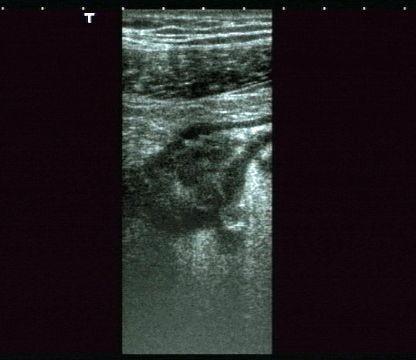

Lo studio medico privato del Dottor Patrizio Stornelli è ad Avezzano è dotato di un'attrezzatura ecografica moderna. Oltre alla ecografia addominale dei parenchimi, si esegue l'ecografia gastroenterolgica ed in particolare l'ecografia del tenue, che consente la diagnosi ed il follow-up particolaremente dei paziente con malattia di Crohn, ma anche l'ecografia del colon. Grazie a questo approccio è possibile scansionare interi segmenti del colon con particolare riguardo alla patologia diverticolare ma anche di indiduare l'appendice e di porre diagnosi di certezza di eventuale appendicite acuta.